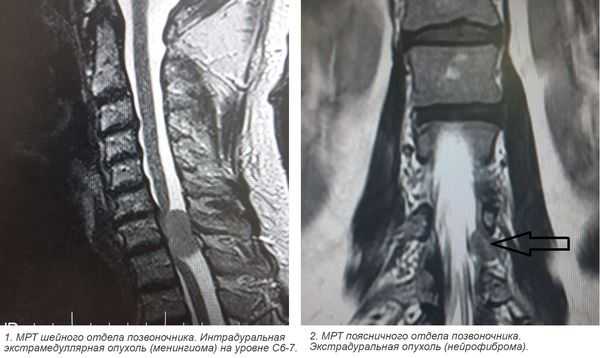

Наиболее безопасным и эффективным способом, позволяющим диагностировать опухоль спинного мозга, выступает МРТ позвоночника. Метод дает возможность послойно визуализировать расположенные в позвоночном столбе мягкотканные образования, проанализировать объем и распространенность опухоли, ее локализацию по отношению к веществу, оболочкам и корешкам спинного мозга, сделать предварительную оценку гистоструктуры новообразования.

3. Магнитно-резонансная томография (МРТ) с контрастным усилением. На данный момент это основной метод диагностики новообразований спинного мозга. МРТ позволяет визуализировать весь спинной мозг и позвоночник и определить локализацию опухоли. Накопление контрастного вещества определяет не только распространение, но и гистологическую структуру опухоли [5] [6] .

МРТ позволяет предположить тип опухоли, определить ее диффузный или фокальный характер, установить точную локализацию и распространенность. Все эти данные необходимы не только с диагностической точки зрения, но и для адекватного планирования хирургического лечения. Т1-режим более информативен в отношении кистозных и солидных составляющих новообразования, Т2-режим — в отношении кист и визуализации цереброспинальной жидкости. Применение контраста значительно облегчает дифференцировку опухоли от окружающих ее отечных тканей.